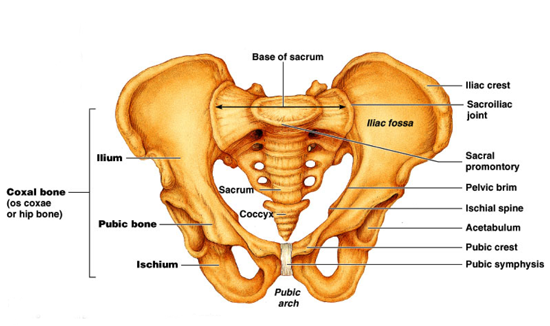

とても興味深いことに、推定年齢を推定するときに専門家は仙腸関節を見て判断するそうです。幼い子どもの仙腸関節はとてもよく動き、成長すると共にその可動性は段々と少なくなり、大人になると動きはだいぶ少なくなります。

構造は2つの寛骨(腸骨+恥骨+坐骨)と真ん中に一つの仙骨で構成されているのが仙腸関節ですが、前側で見ていくと2つの寛骨が前方でくっ付いて、恥骨結合というものになります。

仙腸関節+恥骨結合で骨盤帯という名前になるのですが、骨盤帯の役割としてはお腹の臓器を包み込む容器と、体幹の骨格を構成するのに欠かすことのできない存在です。